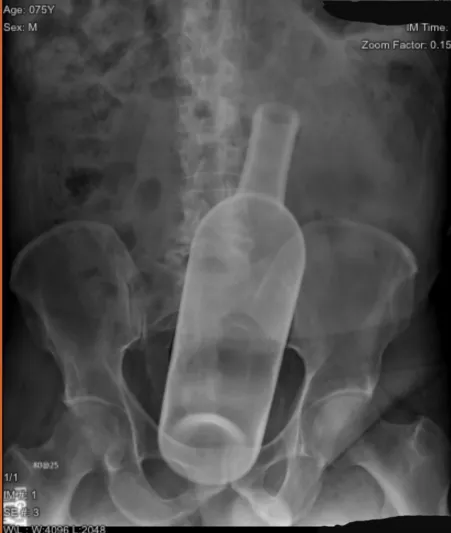

Category: nsfw_wtf